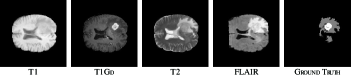

Refer to caption

Figure 11: Typical slices of a patient with four MRI scans and corresponding ground truth.